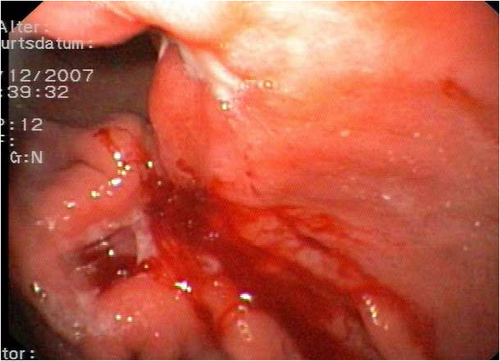

Gastroskopie: Auf Grund des einmaligen Absetzens von Teerstuhl wurde eine Gastroskopie durchgeführt. Es zeigte sich hier ein großer Tumor ca. 5 × 2 cm mit zentraler Ulzeration im Übergang Korpus/Antrum. Der histologische Befund ergab ein Siegelring-Karzinom vom diffusen Typs nach Lauren.